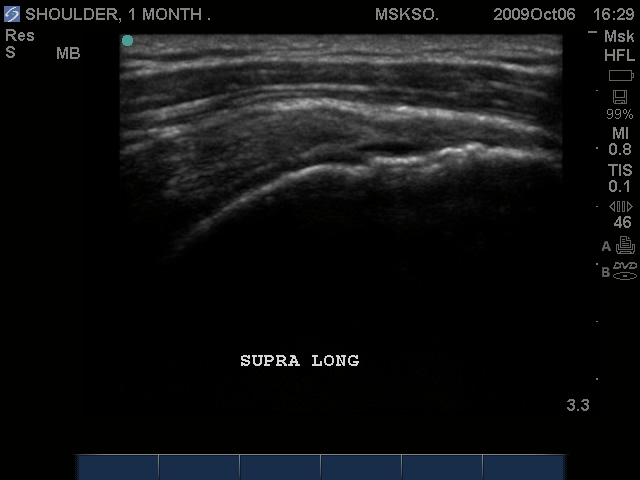

Supraspinatus imaged distally over the Greater Tuberosity. Large articular surface tear measured anterior to posterior, Infraspinatus tendon is seen at the right as a hyperechoic tendon transverse oblique over the posterior humeral head.

Long axis Supraspinatus tendon over lateral Greater Tuberosity. (lateral greater tuberosity is flat relative to the anterior) Tendon retraction is seen over cartilage interface sign of the humeral head.